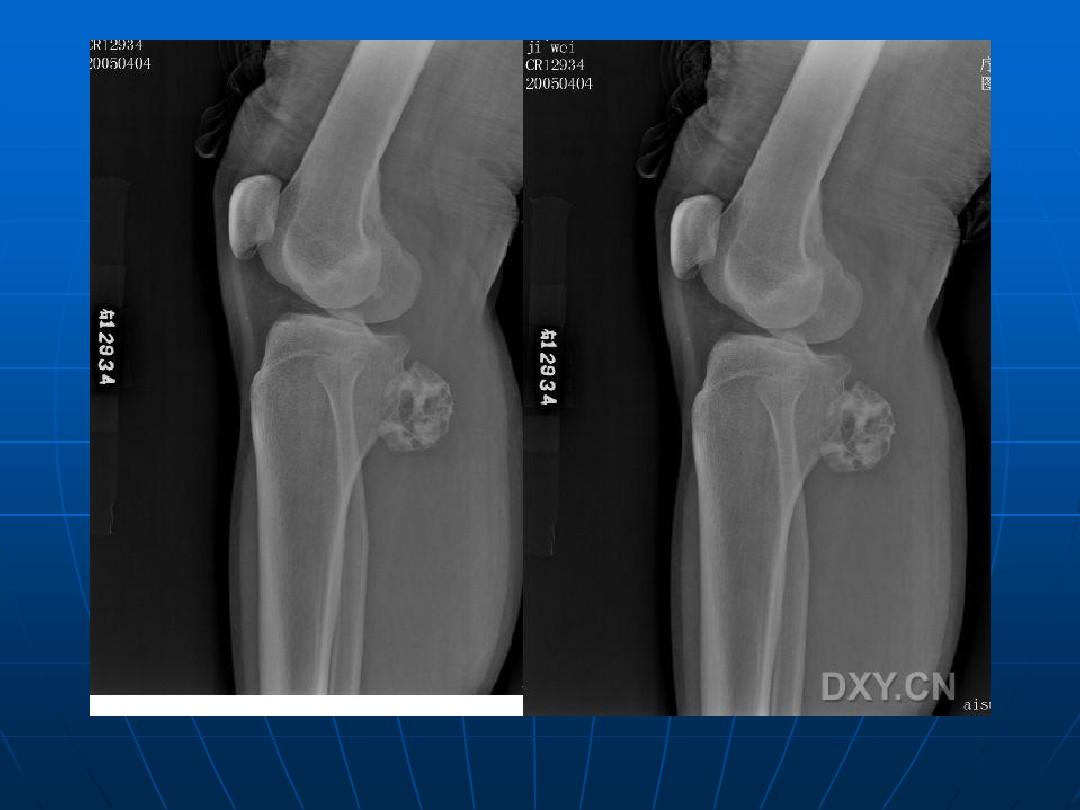

③惡變成周圍型軟骨肉瘤的發(fā)生率高。應(yīng)與軟骨肉瘤,纖維肉瘤相鑒別軟骨肉瘤在x線照片上的顯影頗不一致。有時長骨的干骺端被腫瘤組織破壞而呈透明的假囊腫樣,囊內(nèi)散在少許鈣化點(diǎn)和骨化。有時瘤組織所產(chǎn)生的大量棉絮狀鈣化塊遮蔽著被破壞的骨缺損處,而形成致密的鈣化陰影。骨軟骨瘤的惡變起始于腫瘤的軟骨帽和其纖維包膜(參閱骨軟骨瘤),軟骨細(xì)胞分裂和軟骨鈣化作用驟然增加,以致在x線照片上發(fā)現(xiàn)多量如棉絮狀不規(guī)則的鈣化點(diǎn),散在于骨軟骨瘤遠(yuǎn)端周圍的軟組織腫塊中。放射樣的骨膜反應(yīng)性新骨增生則不多見,有時或可發(fā)現(xiàn)骨膜三角。當(dāng)軟骨瘤惡變時,骨內(nèi)的溶骨性陰影增大,鈣化點(diǎn)增多,聚集成堆。腫瘤組織有時穿透皮質(zhì)骨,在軟組織中發(fā)展并形成鈣化陰影。皮質(zhì)骨外可能發(fā)生日光放射樣骨膜新生骨反應(yīng)。